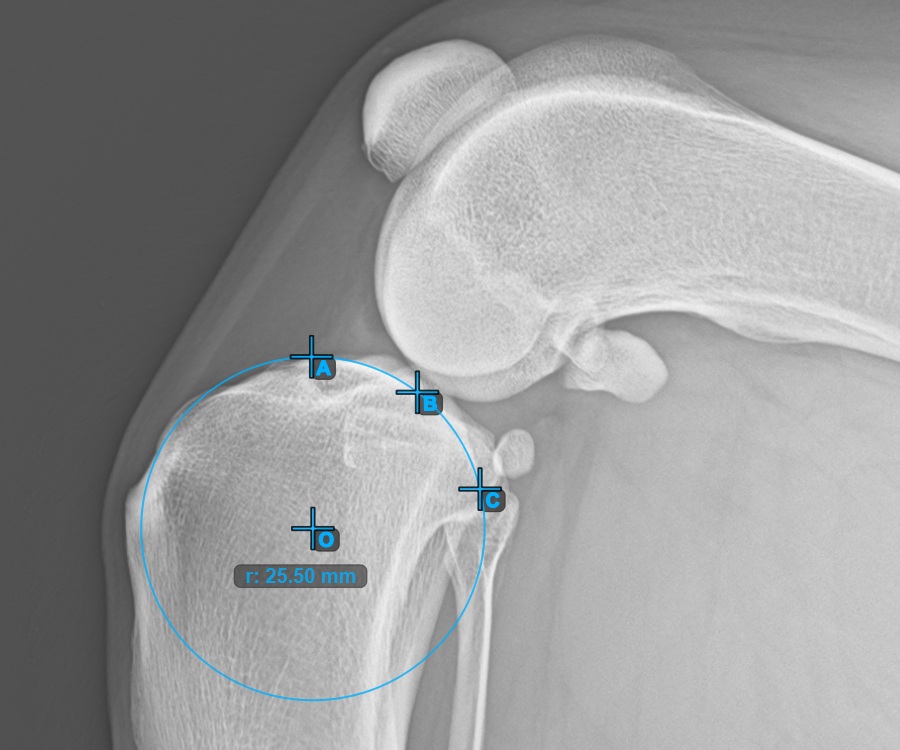

The image below represents a typical placement of the three points on the second Condylus Femoris.

![]()

Mark one point in front of the joint on the common tangent between the two main condylus circles. A line will be drawn automatically through the marked point.